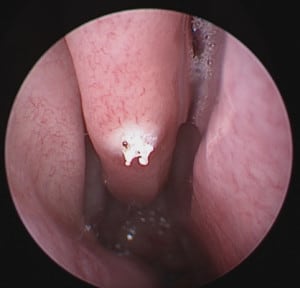

Picture below shows a bleeding point on the right middle turbinate within the nose. This was cauterized to stop the bleeding.